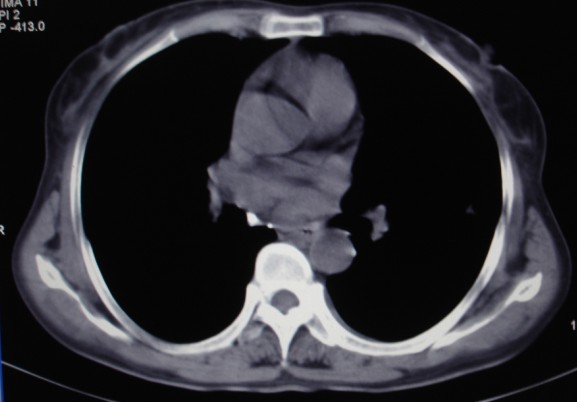

女,60岁咳嗽咳痰7天,痰中带血,有发热史,血象大约6000

双肺多发病灶,呈多形性,多叶分布,左上叶尖后段靠胸壁病灶伴有空洞,边缘模糊,与胸壁呈刀切征.

考虑混合感染以tb为主.

双肺tb并左肺下叶空洞形成可能性大,建议痰检。期待结果

多灶,多形,少聚,少块。卫星灶,空洞影,树芽征,结核可能性大